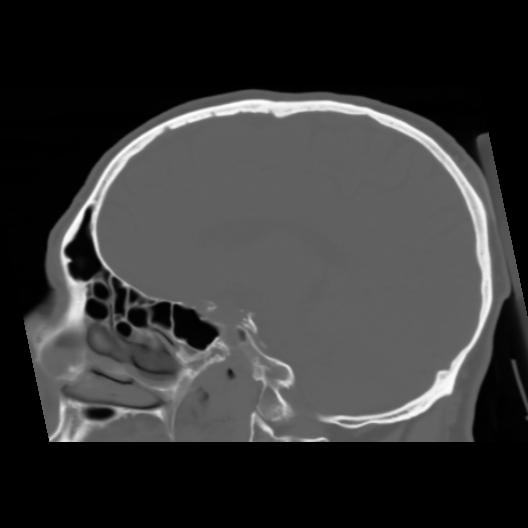

6 CEREBRO,,Sagittal,3.000,CEREBRO,Sagittal,